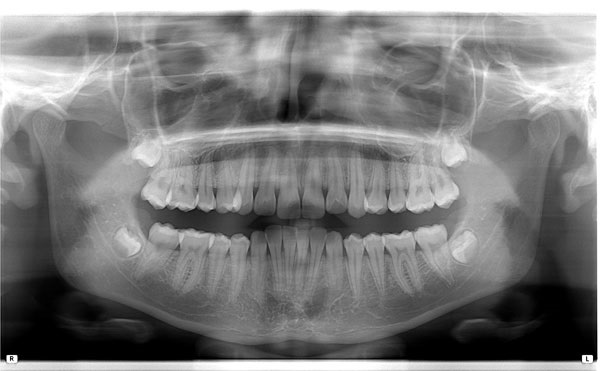

Панорамна снимка

Панорамна снимкаРегистрира общото състояние на съзъбието и пародонта. Чрез нея се прави план за лечение и различни контроли. Ползва се и в имплантологията. Детска панорамна снимкаРегистрира общото състояние на съзъбието, наличие на зародиши, аномалии. Чрез нея се прави ортодонтско планиране за корекция на захапката. ТелерентгенографияСнимка в профил на лицевия череп. Използва се за анализ на захапката. СинусиПредава детайлна информация за състоянието на синусите. ОртосинусиСнимка на максиларните синуси за целите на денталната медицина. Снимка на темпоро-мандибуларните ставиИзползва се за оценка на промени в челюстните стави. |